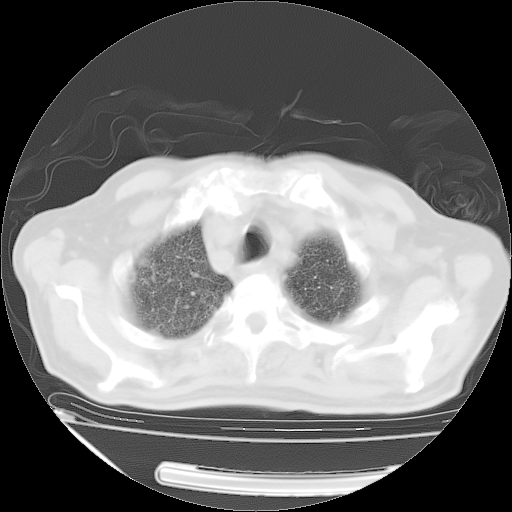

甲强龙80mg/日+抗结核治疗(异烟肼+利福霉素+乙胺丁醇)10天。复查肺部CT。

治疗10天肺部CT